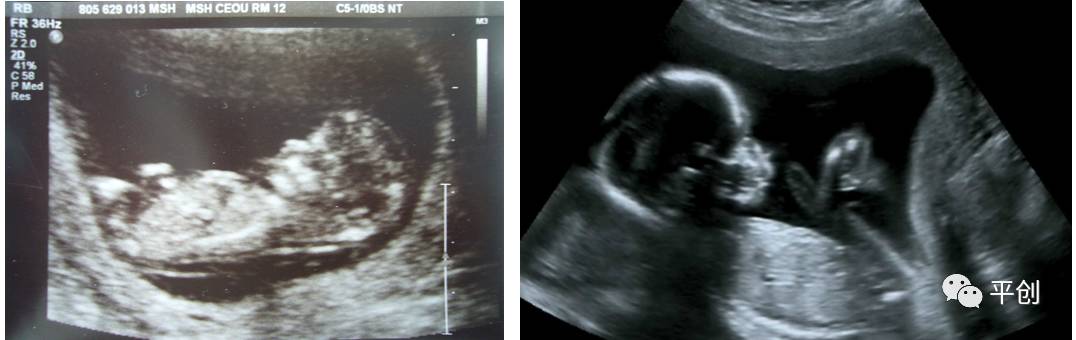

更準(zhǔn)確的醫(yī)學(xué)診斷,來自B超檢查結(jié)果的輔助,準(zhǔn)確的B超檢查結(jié)果,來自B超醫(yī)生看到的B超圖像,清晰的B超成像,來自好的耦合劑。所以說,好的耦合劑對B超的成像很重要。

而影響B(tài)超檢查成像的因素有兩點(diǎn),一是來自好的探頭,二是來自優(yōu)質(zhì)的耦合劑。如果這兩個(gè)產(chǎn)品其中有一個(gè)質(zhì)量不過關(guān),即對B超成像有一定程度的影響,可能會(huì)有成像不清楚,醫(yī)生無法準(zhǔn)確判斷所檢查器官的實(shí)際病變,嚴(yán)重的有可能度至醫(yī)生誤診的后果。

普通的卡波姆,其透聲力沒達(dá)到超聲波傳導(dǎo)的系數(shù),無法有效地傳達(dá)聲波,同時(shí)沒有良好的偶合功能,這種情況下,就無法形成清晰的圖像 。

另外,有的廠家的耦合劑濃度太高,或是太稀,涂在檢查部位上,馬上就有一部分水流出,讓患者感到很不舒服,而過稀的耦合劑會(huì)減低其偶合性,過濃的耦合劑難以展開涂抺,或涂抺不均勻,影響探頭在檢查部位的滑動(dòng),這兩種情況都會(huì)減低B超中的耦合性,影響B(tài)超成像的清晰度,從而影響醫(yī)生看到的結(jié)果而給出錯(cuò)誤的判斷,甚至間接的引發(fā)了醫(yī)療事故,嚴(yán)重地影響了醫(yī)院的專業(yè)度和信服力。這些都是醫(yī)生和醫(yī)院及患者都不希望發(fā)生的。

所生產(chǎn)出來的耦合劑無雜質(zhì)、透明度高、不易干,不化水,易偶合、易擦凈,透聲性超過國家標(biāo)準(zhǔn)的50%(數(shù)據(jù)通過國家指定的第三方檢測機(jī)構(gòu)檢測結(jié)果所得),完全地解決了成像不清晰的難題。

安創(chuàng)安必潔耦合劑已經(jīng)在廣東省人民醫(yī)院、南方醫(yī)院、中山大學(xué)附屬第一醫(yī)院等全國各三甲醫(yī)院使用,并得到了各醫(yī)院的一致認(rèn)可,解決了其它品牌耦合劑的偶合性差、透聲功能低,成像不清晰的問題,減少了B超結(jié)果誤診的機(jī)率,同時(shí)也解決了短期內(nèi)要多次尋找耦合劑品牌的煩惱,所以得到了各合作醫(yī)院的聯(lián)合推薦使用:“好的耦合劑,選用安創(chuàng)安必潔消毒耦合劑。